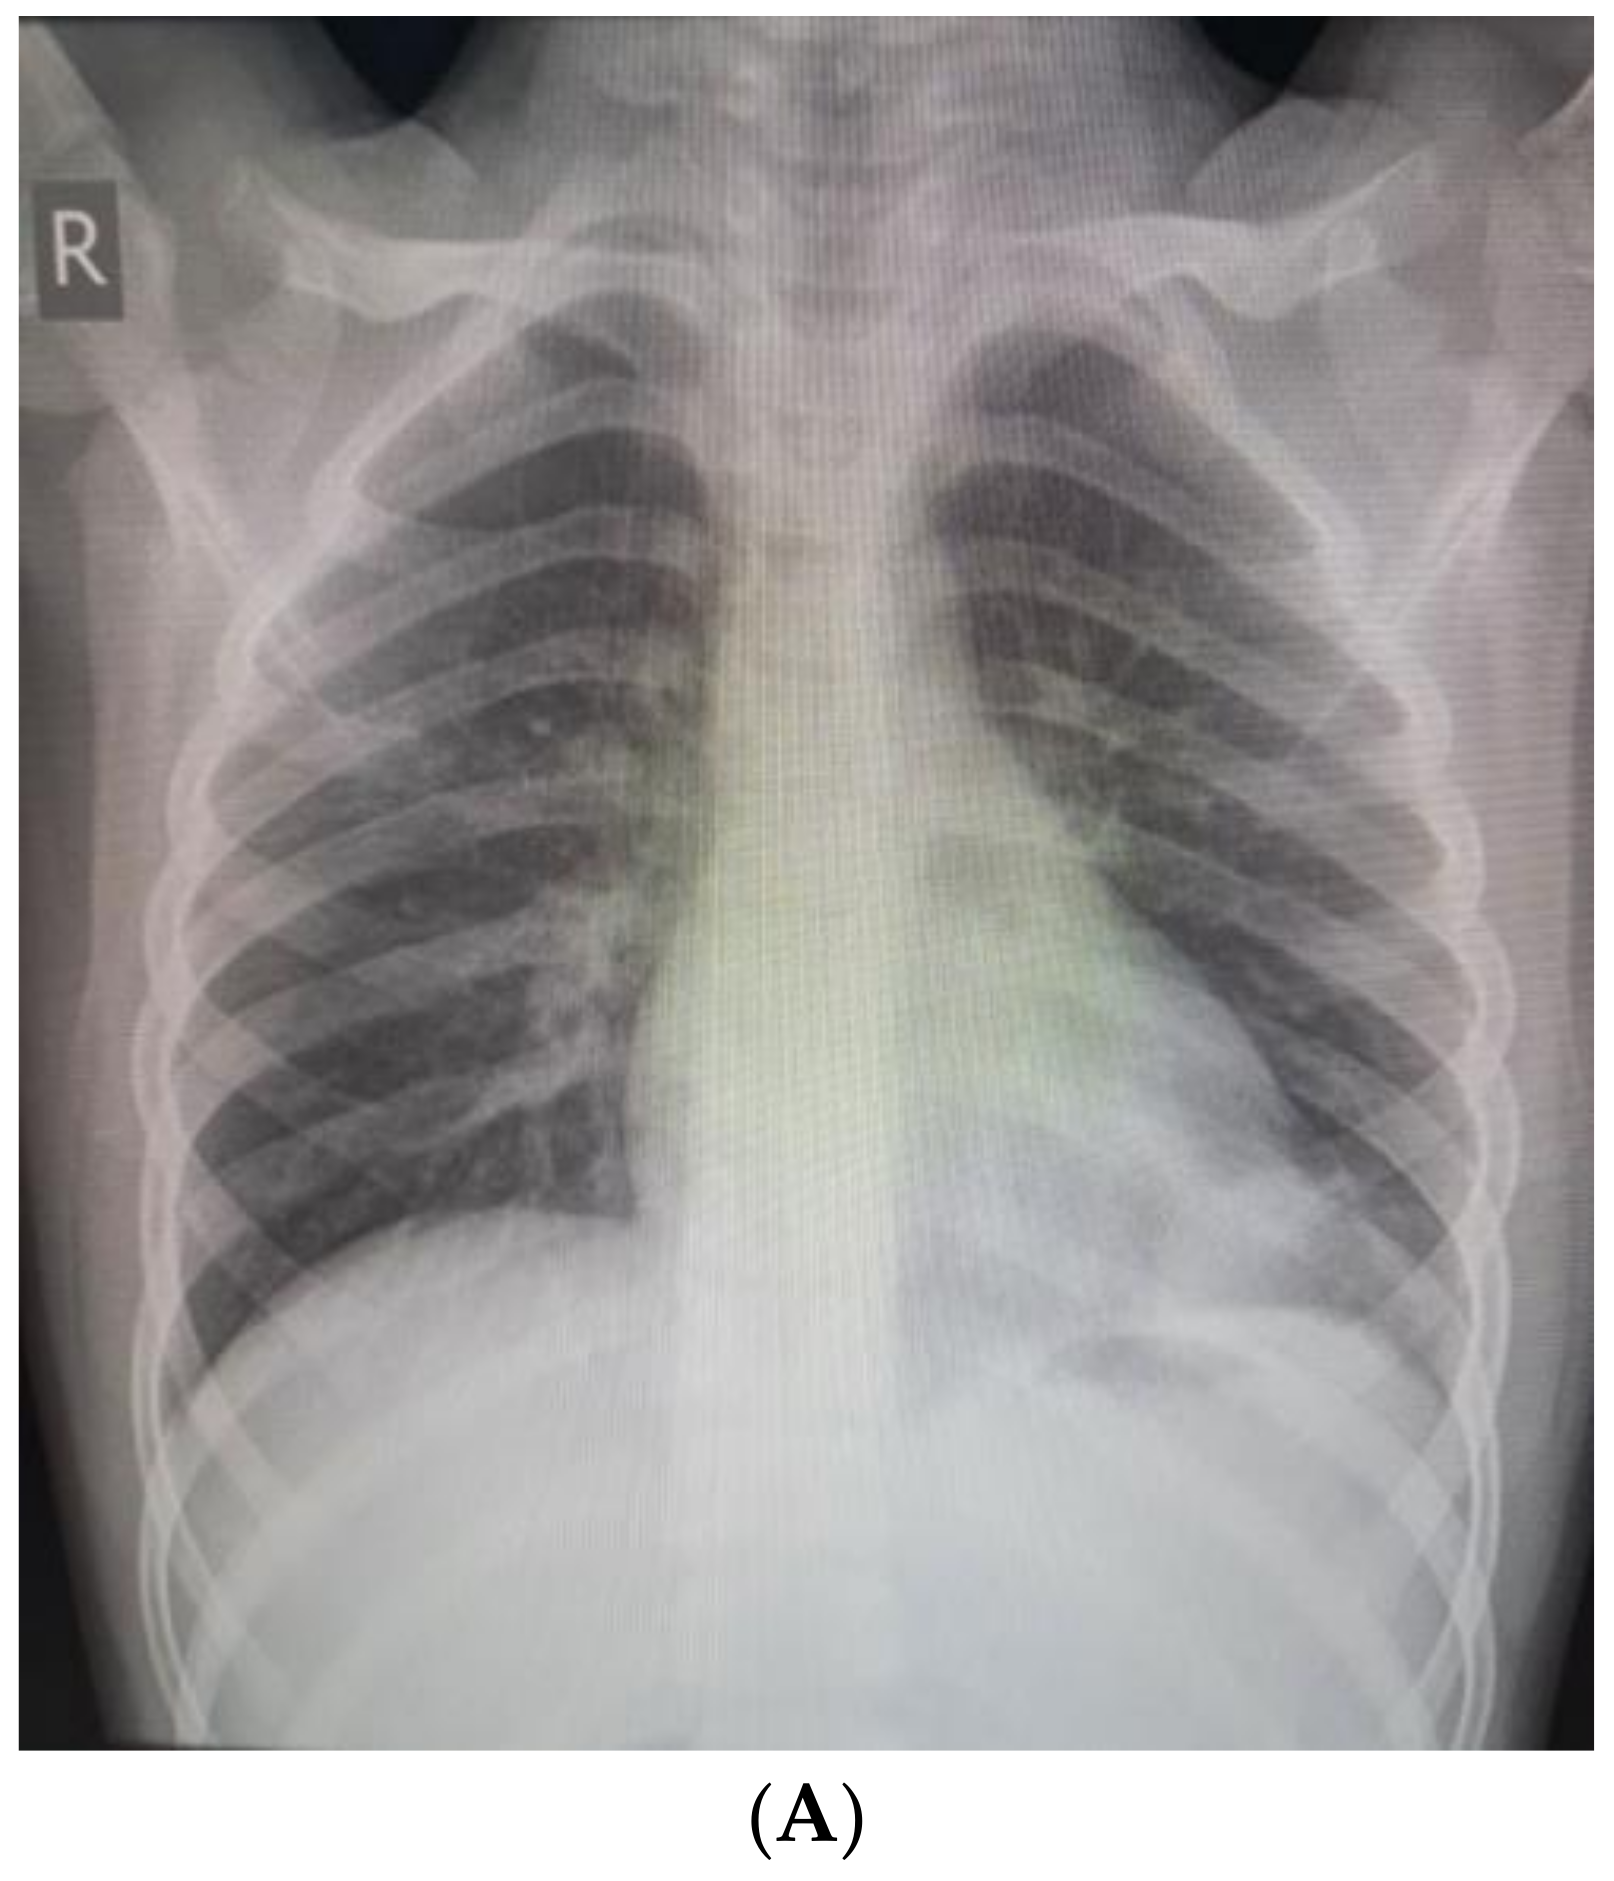

We present a 9-year-old boy with a history of recurrent respiratory infections. In July 2022, the child swallowed an awn during a walk on a field in Northwest Bulgaria, and after two days, he started to cough. On the third day after the accident, he became febrile, and antibiotic therapy was prescribed (Clarithromycin). This treatment was not effective, and the child suffered left-sided chest pain, irradiating to his left shoulder. Nonsteroidal anti-inflammatory drugs were prescribed. On the 10th day, the patient was admitted to the Department of Pediatric Pulmonology for further diagnostic workup and treatment. The child’s condition was stable, with a productive cough and reduced vesicular breathing paravertebrally and axillary on the left side of the chest. His hemodynamic was stable, and his abdomen was not tender, without hepatosplenomegaly. His blood tests showed inflammation—increased C-reactive protein (CRP) 36.29 mg/L and leukocytes 10,9 x109 L, and stable hematological parameters (hemoglobin 126 g/L, hematocrit 39%, erythrocytes count range 4.69, platelets 347). Biochemical markers were also in the normal range—sugar level 6.08 mmol/L, creatinine 42 µmol/L, urea 2 mmol/L, ASAT 15 U/L, ALAT 12 U/L, alkaline phosphatase 127 U/L, total protein 65.3 g/L, albumin 41.26 g/L. Frontal and lateral chest X-rays showed faint reticular and patchy opacities with unclear margins in the lower lobe of the left lung (Figure 1A,B). Treatment comprised antibiotics (Ceftriaxone), corticosteroids (Methylprednisolone), and saline inhalations.

Figure 1. (A). Frontal chest X-ray—faint reticular and patchy opacities with unclear margins were visualized in the lower lobe of the left lung. (B). Lateral chest X-ray.